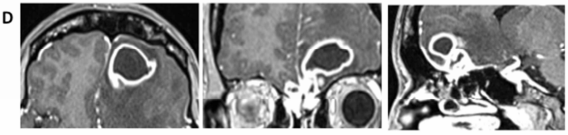

在失眠中煎熬了半年,我的后脑勺炸开剧痛,像有人用铁锤敲打我的脑袋。2013年9月,立刻前往医院检查,医生告诉我,我脑子里长个了东西。头颅 CT 及 MRI 显示:嗅沟区占位病变,向右筛板延伸,并伴额-嗅区双侧硬脑膜增强(图 1A)。

图1A:2013年9月,影像学首次确诊时